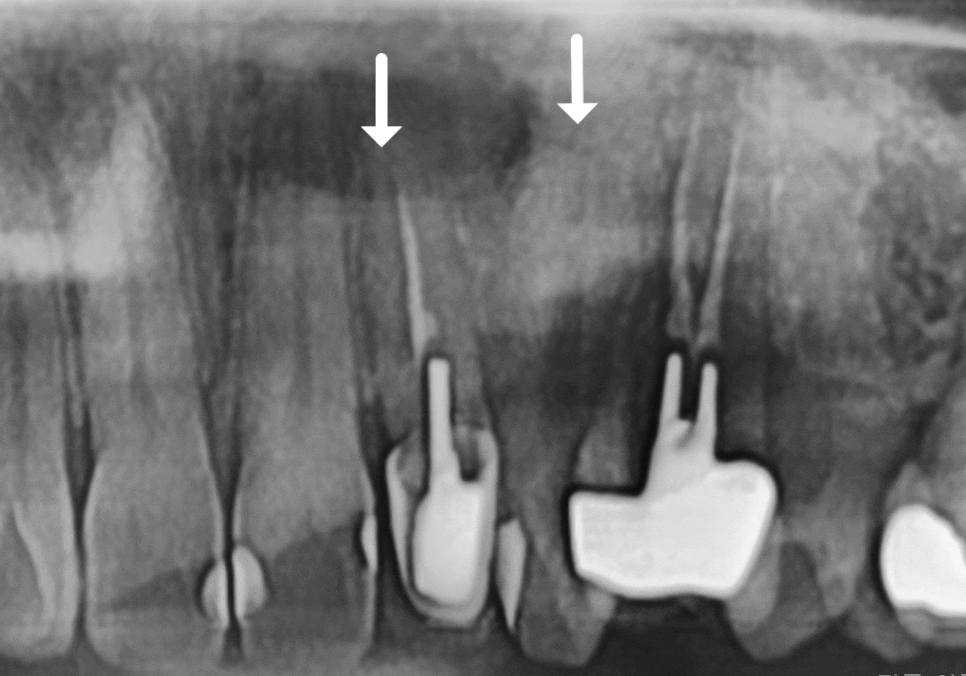

CT 검사 결과를 보니 상태가 꽤 심각했습니다.

왼쪽 앞니(#22) 뿌리 끝 염증이 너무 커져서

주변 잇몸뼈를 대부분 녹여버린 상태였거든요.

사진 속에서 유독 까맣게

빈 공간처럼 보이는 부분이 혹시 보이시나요?

231129

바로 그 부분이 염증이 깊게 자리 잡아

뼈가 녹은 건데요~

이 염증 주머니가 옆 치아(#23)의 뼈까지

침범하며 녹이고 있는 상태였어요.ㅜㅜ

원인을 꼼꼼히 살펴보니,

예전 치료 때 신경관 끝부분까지 재료가

끝까지 채워지지 않았던 것이 문제였어요.

그 미세한 틈 사이로 세균이 번식하면서

염증이 걷잡을 수 없이 커진 것이죠.